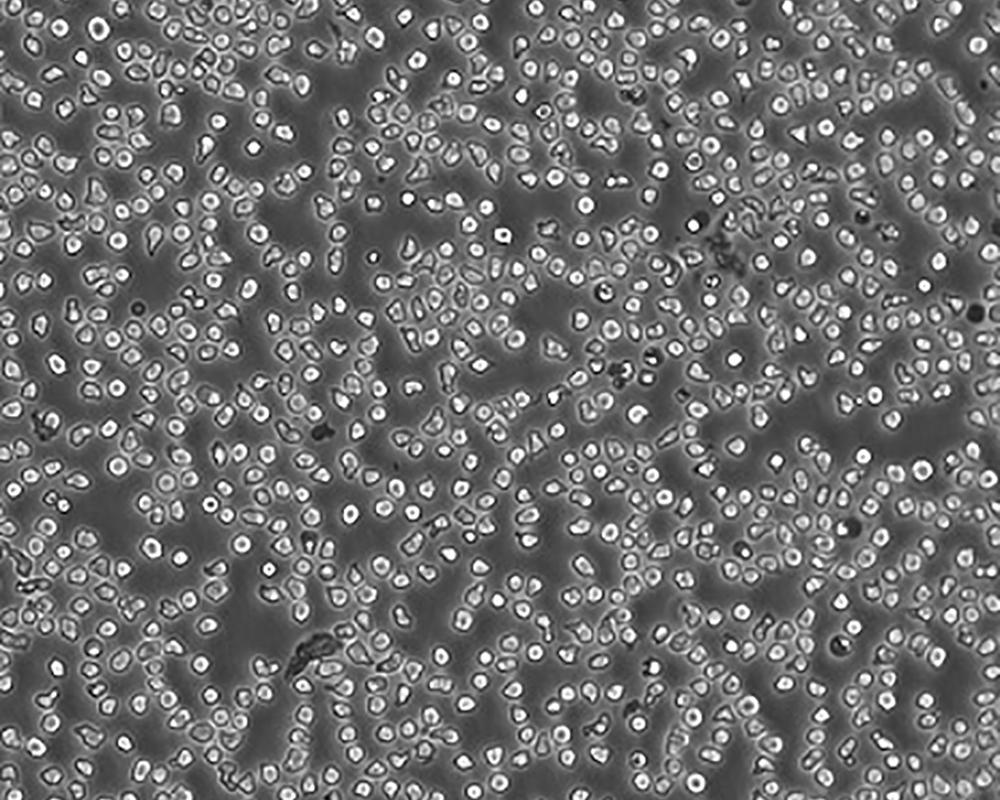

生長特性 suspension

形態特征 lymphoblast

傳代方法 Maintain cell density between 2×10^4 and 4×10^4 viable cells/mL.

細胞描述 一位套細胞淋巴瘤患者的巨細胞變種顯示白血病轉變,從其外周血單核細胞出發建立了MCL細胞株JeKo-1。 JeKo-1細胞EB病毒陰性,并表達一種B細胞表型的IgM。 細胞過表達cyclin D1, Bcl-2, c-Myc 及 Rb 蛋白。 Bcl-1/J(H)基因重排得到了PCR證實。 JeKo-1細胞在SCID小鼠中高成瘤。 [PubMed: 9753063]